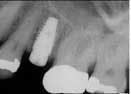

The first procedure that I would like to review is called the 3 in 1 Implant Procedure. Many GPs call this the 5-minute Implant, Abutment and Crown procedure. This simply means that what used to take implant dentists three appointments to accomplish is now accomplished in one, relatively brief, single appointment. It is a huge benefit to your patients because there is less time investment in the dental office and there is typically much less discomfort associated with the procedure. The reduction in discomfort is largely related to the usage of one of the top five minimally invasive, no suture, soft-tissue accesses. Remember, bone is not innervated, nerves may travel through the bone but do not directly innervate. Any discomfort related to an implant procedure postsurgically is caused by soft tissue. When we provide less invasive surgery, we reduce soft tissue involvement and thus pain. The three in one implant procedure is applicable for almost any edentulous area in the mouth that is suitable. The initial soft-tissue access and first 2 to 5 mm of the pilot hole in bone are created using a circular motion with the high-speed handpiece and a Duo-bur. Final osteotomy is created and the implant is placed. Immediately after implant placement, a final impression is taken after customizing a straight stock abutment, placing wax in the top of the abutment, and taking a standard check bite or full tray impression.

Of all of the advances made in implant dentistry over the last 10 years, the No-Drill Implant Procedure, using an Osteoconverter, has had the greatest impact on the general practitioner’s productivity and patient satisfaction. Immediately after extracting a tooth, an Osteoconverter is inserted with a spiraling motion into the socket, which achieves two important tasks: 1. The PDL is scored in roughly 2 mm increments allow,ing blood flow and highly bone forming cells to enter the site. 2. The unique curvature of the root is "converted" to a cylindrical shape, which allows for an implant-worthy osteotomy. The Osteoconverter doubles as OsteoReady's Prestige series implant. Clinicians who place OsteoReady implants may leave the Osteoconverter in place after inserting to serve as the final implant. The Prestige implant doubles as an instrument, the Osteoconverter which is a hybrid between a bone condenser and osteotomb. If the clinician uses another company's implant, simply use the Osteoconverter to convert the site, remove the Osteoconverter by unscrewing counterclockwise and insert a final implant. The majority of GPs who learn this procedure are able to immediately incorporate it into their busy practices. In many practices, about 50% of extractions have transformed to extraction and implant cases using the No-Drill Implant Procedure. Undoubtedly, the extraction takes more time to complete than the implant procedure. Join the hundreds of GPs who are successfully placing no drill implants in their practices using the Osteoconverter.

The third and final procedure that is transforming GP practices around the nation is the 1-Drill Implant Procedure. Quite simply, instead of the clinician going through a series of four or five drills to complete one osteotomy, one drill is used to complete the final osteotomy. The drill is called a multi-drill and has the widths of four to five drills built into the drill. This procedure is transforming the versatility of implantology in the general dental practice much like recent advances in endodontics have benefitted the general practitioner. The one-drill implant may be placed into an immediate extraction site or an area that has been edentulous for the short or long term. The 1-drill procedure relies on two important variables: 1. The drill used must be end-cutting, side-/axial-cutting, and have a modified taper (6% is ideal). 2. The implant used with the 1-drill procedure should ideally have aggressive threading, a 6% taper, and be self-tapping. (OsteoReady's Prestige series implants are approved for this procedure.) By utilizing a tapered drill, the osteotomy is wider toward the coronal aspect (more dense cortical plate bone) and more narrow apically (generally softer type 2/3 bone). Maxillary 1-drill implants are inserted using the same tool that is used with the No Drill Procedure (Prestige series). If the site has been edentulous for more than six weeks, then an impression for the final crown may be taken immediately after the implant is placed. The typical implant placed with this procedure takes less time to complete than an occlusal composite. That gives us as clinicians the opportunity to provide for a much more reasonable fee for those in need.